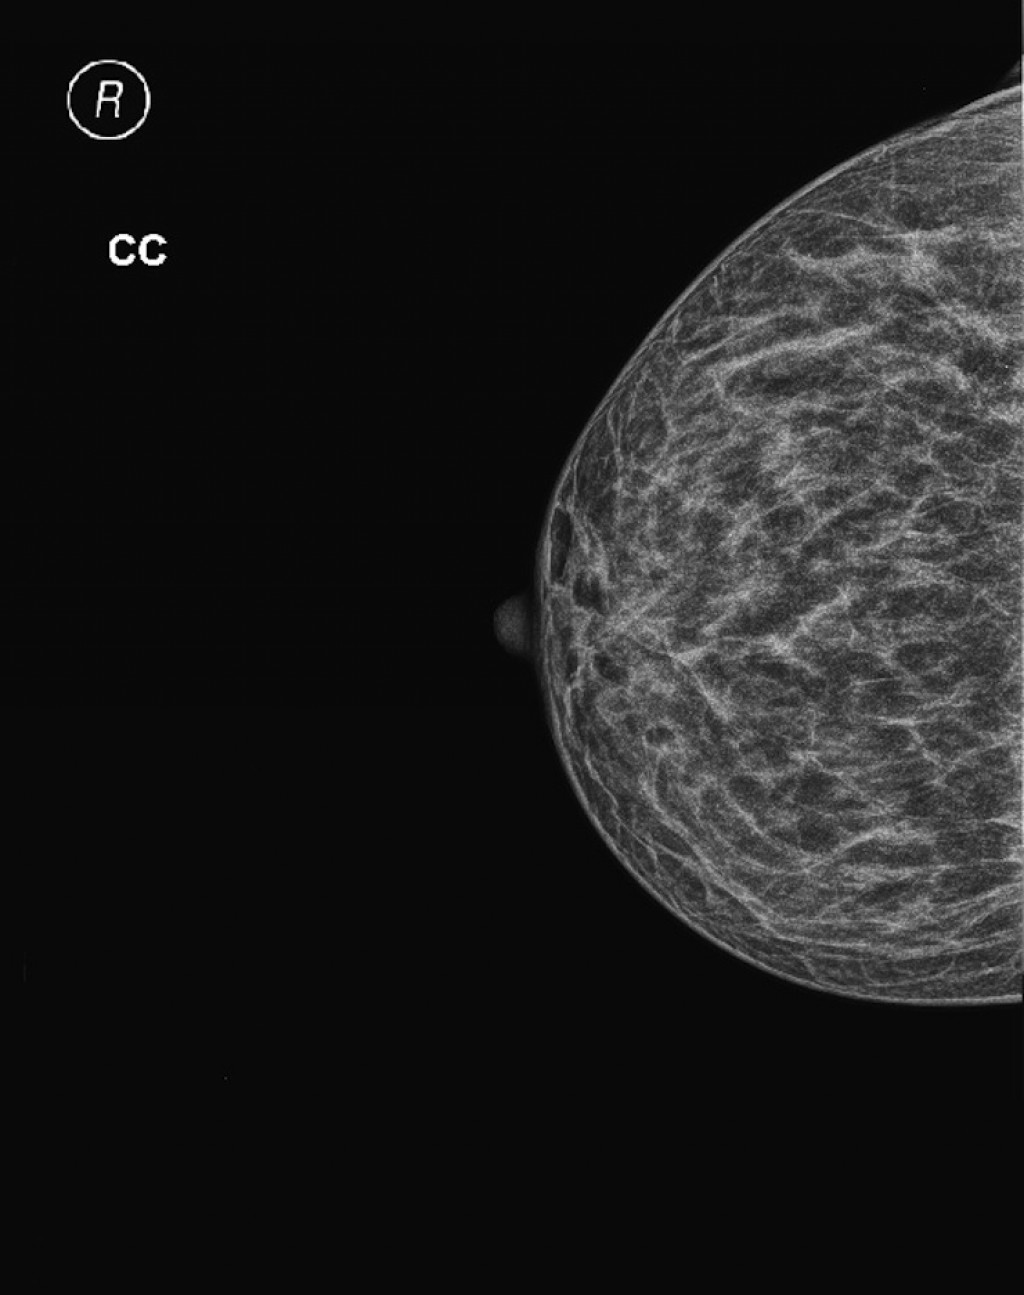

Фиброаденома молочной железы - доброкачественное образование, которое часто встречается у женщин. Оно может быть обнаружено при помощи различных методов диагностики, включая маммографию. Ниже представлены фотографии, помогающие понять, как выглядит данное заболевание.

Маммография и ее роль в диагностике фиброаденомы молочной железы

Маммография - это рентгенологическое исследование молочных желез. Оно позволяет выявить различные изменения в тканях, включая фиброаденому. На маммограммах можно увидеть структурные особенности опухоли и отследить ее динамику во времени.